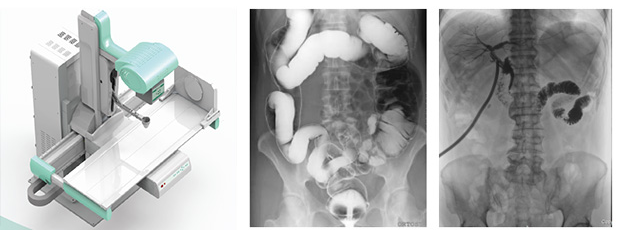

只需一塊動(dòng)態(tài)平板探測(cè)器,即可高效輕松實(shí)現(xiàn)攝影、透視和造影功能,幾乎可以滿足醫(yī)院全科室的臨床檢查需求。

1)大視野無遺漏

17*17英寸的高清像素動(dòng)態(tài)平板探測(cè)器,能對(duì)胸部、腹部等部位實(shí)現(xiàn)大范圍全覆蓋,動(dòng)靜態(tài)之間無感切換。透視檢查無須對(duì)患者重新定位便可觀察到足夠大的人體器官組織,避免漏診誤診。更好地減少了曝光時(shí)間,也減少了病人的輻射劑量。

大尺寸動(dòng)態(tài)平板技術(shù),覆蓋檢查面積范圍廣,輕松實(shí)現(xiàn)胃十二指腸等大面積造影,無需移動(dòng)即可觀看整個(gè)動(dòng)態(tài)過程,避免噪點(diǎn)對(duì)圖像的影響。

2)圖像質(zhì)量無畸變,無失真

高效動(dòng)態(tài)平板技術(shù),圖像不會(huì)有幾何畸變,提供高分辨率和精確的圖像,為臨床診斷提供精準(zhǔn)依據(jù)。